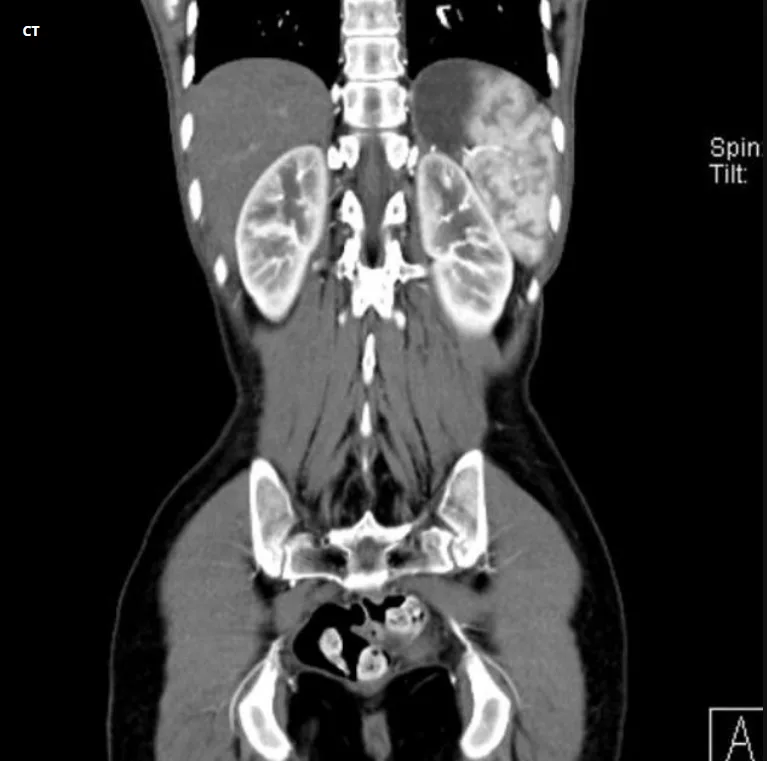

CT Whole Abdomen Scan in Navi Mumbai | Henotic Diagnostics

Looking for a CT Whole Abdomen scan in Kharghar? Henotic Diagnostics offers advanced multi-slice CT scans for the liver, pancreas, kidneys, intestines, spleen, and pelvic organs. Furthermore, this scan helps detect abdominal pain, tumors, infections, kidney stones, liver diseases, and gastrointestinal issues with high precision. In addition, our expert radiologists provide fast reports and accurate results using low-radiation, high-resolution CT technology. Similarly, services are available in Kharghar, Panvel, Belapur, Nerul, Vashi, and Navi Mumbai. Therefore, book your CT Whole Abdomen scan near you today!